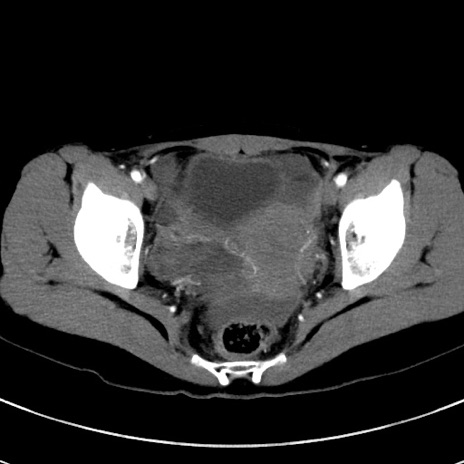

症例17(横断像)

【症例】20歳代女性

【主訴】嘔吐、下腹部痛

【現病歴】昨日夕食後に嘔吐し下腹部痛が出現。本日になっても嘔吐持続し改善しないため来院。

【身体所見】意識清明、BT 37.2℃、BP 108/67mmHg、腹部:平坦、やや硬、下腹部正中から右にかけて圧痛あり、反跳痛軽度あり、tapping pain(+)。

【データ】WBC 13600、CRP 14.94